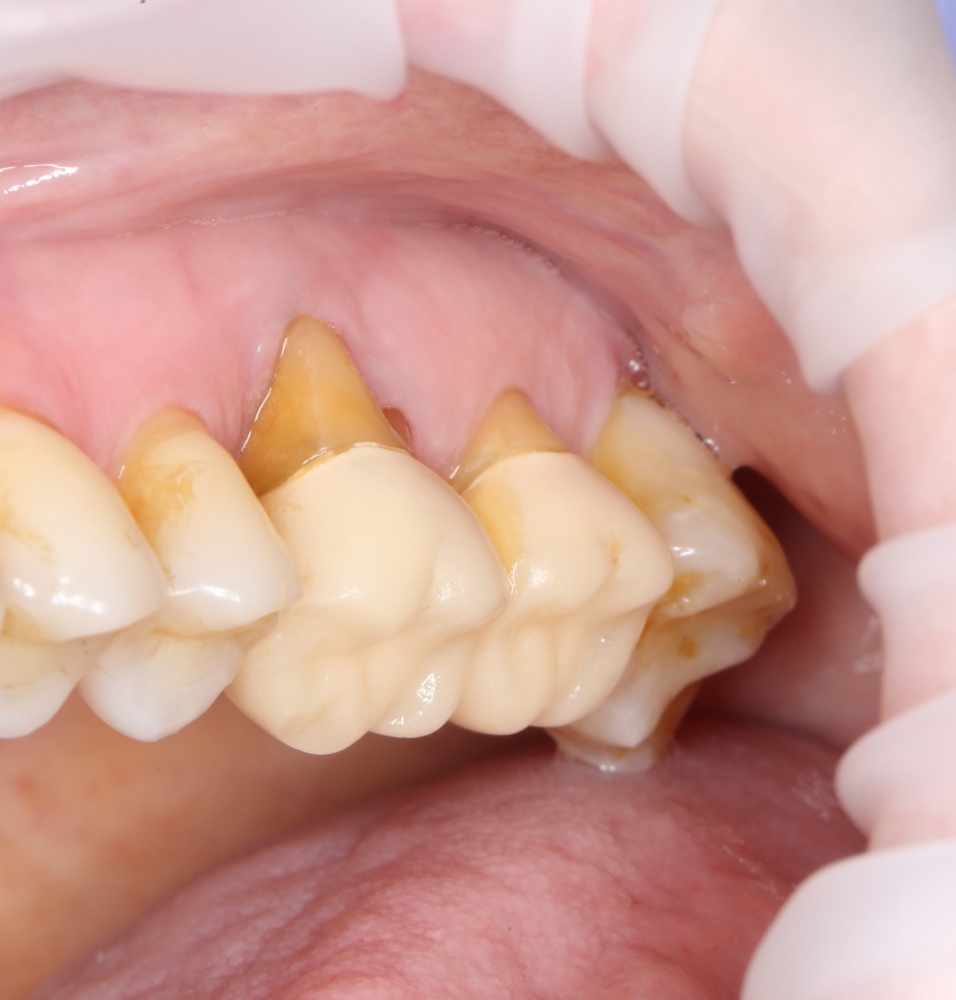

Вот клиническая картина через 4 месяца после ранее проведенной имплантации с остеопластикой:

Как видишь, коллеги из недалекой дружественной страны не осилили снятие швов. Мне это не нравится, хотя и объясняет, почему люди готовы ехать за тыщи километров ради 20-минутной операции удаления зуба мудрости.

Ну хорошо. Швы сняли. Делаем разрез. Обрати внимание, что после всех проведенных операций у нас остается очень небольшой по ширине слой жевательной слизистой оболочки: